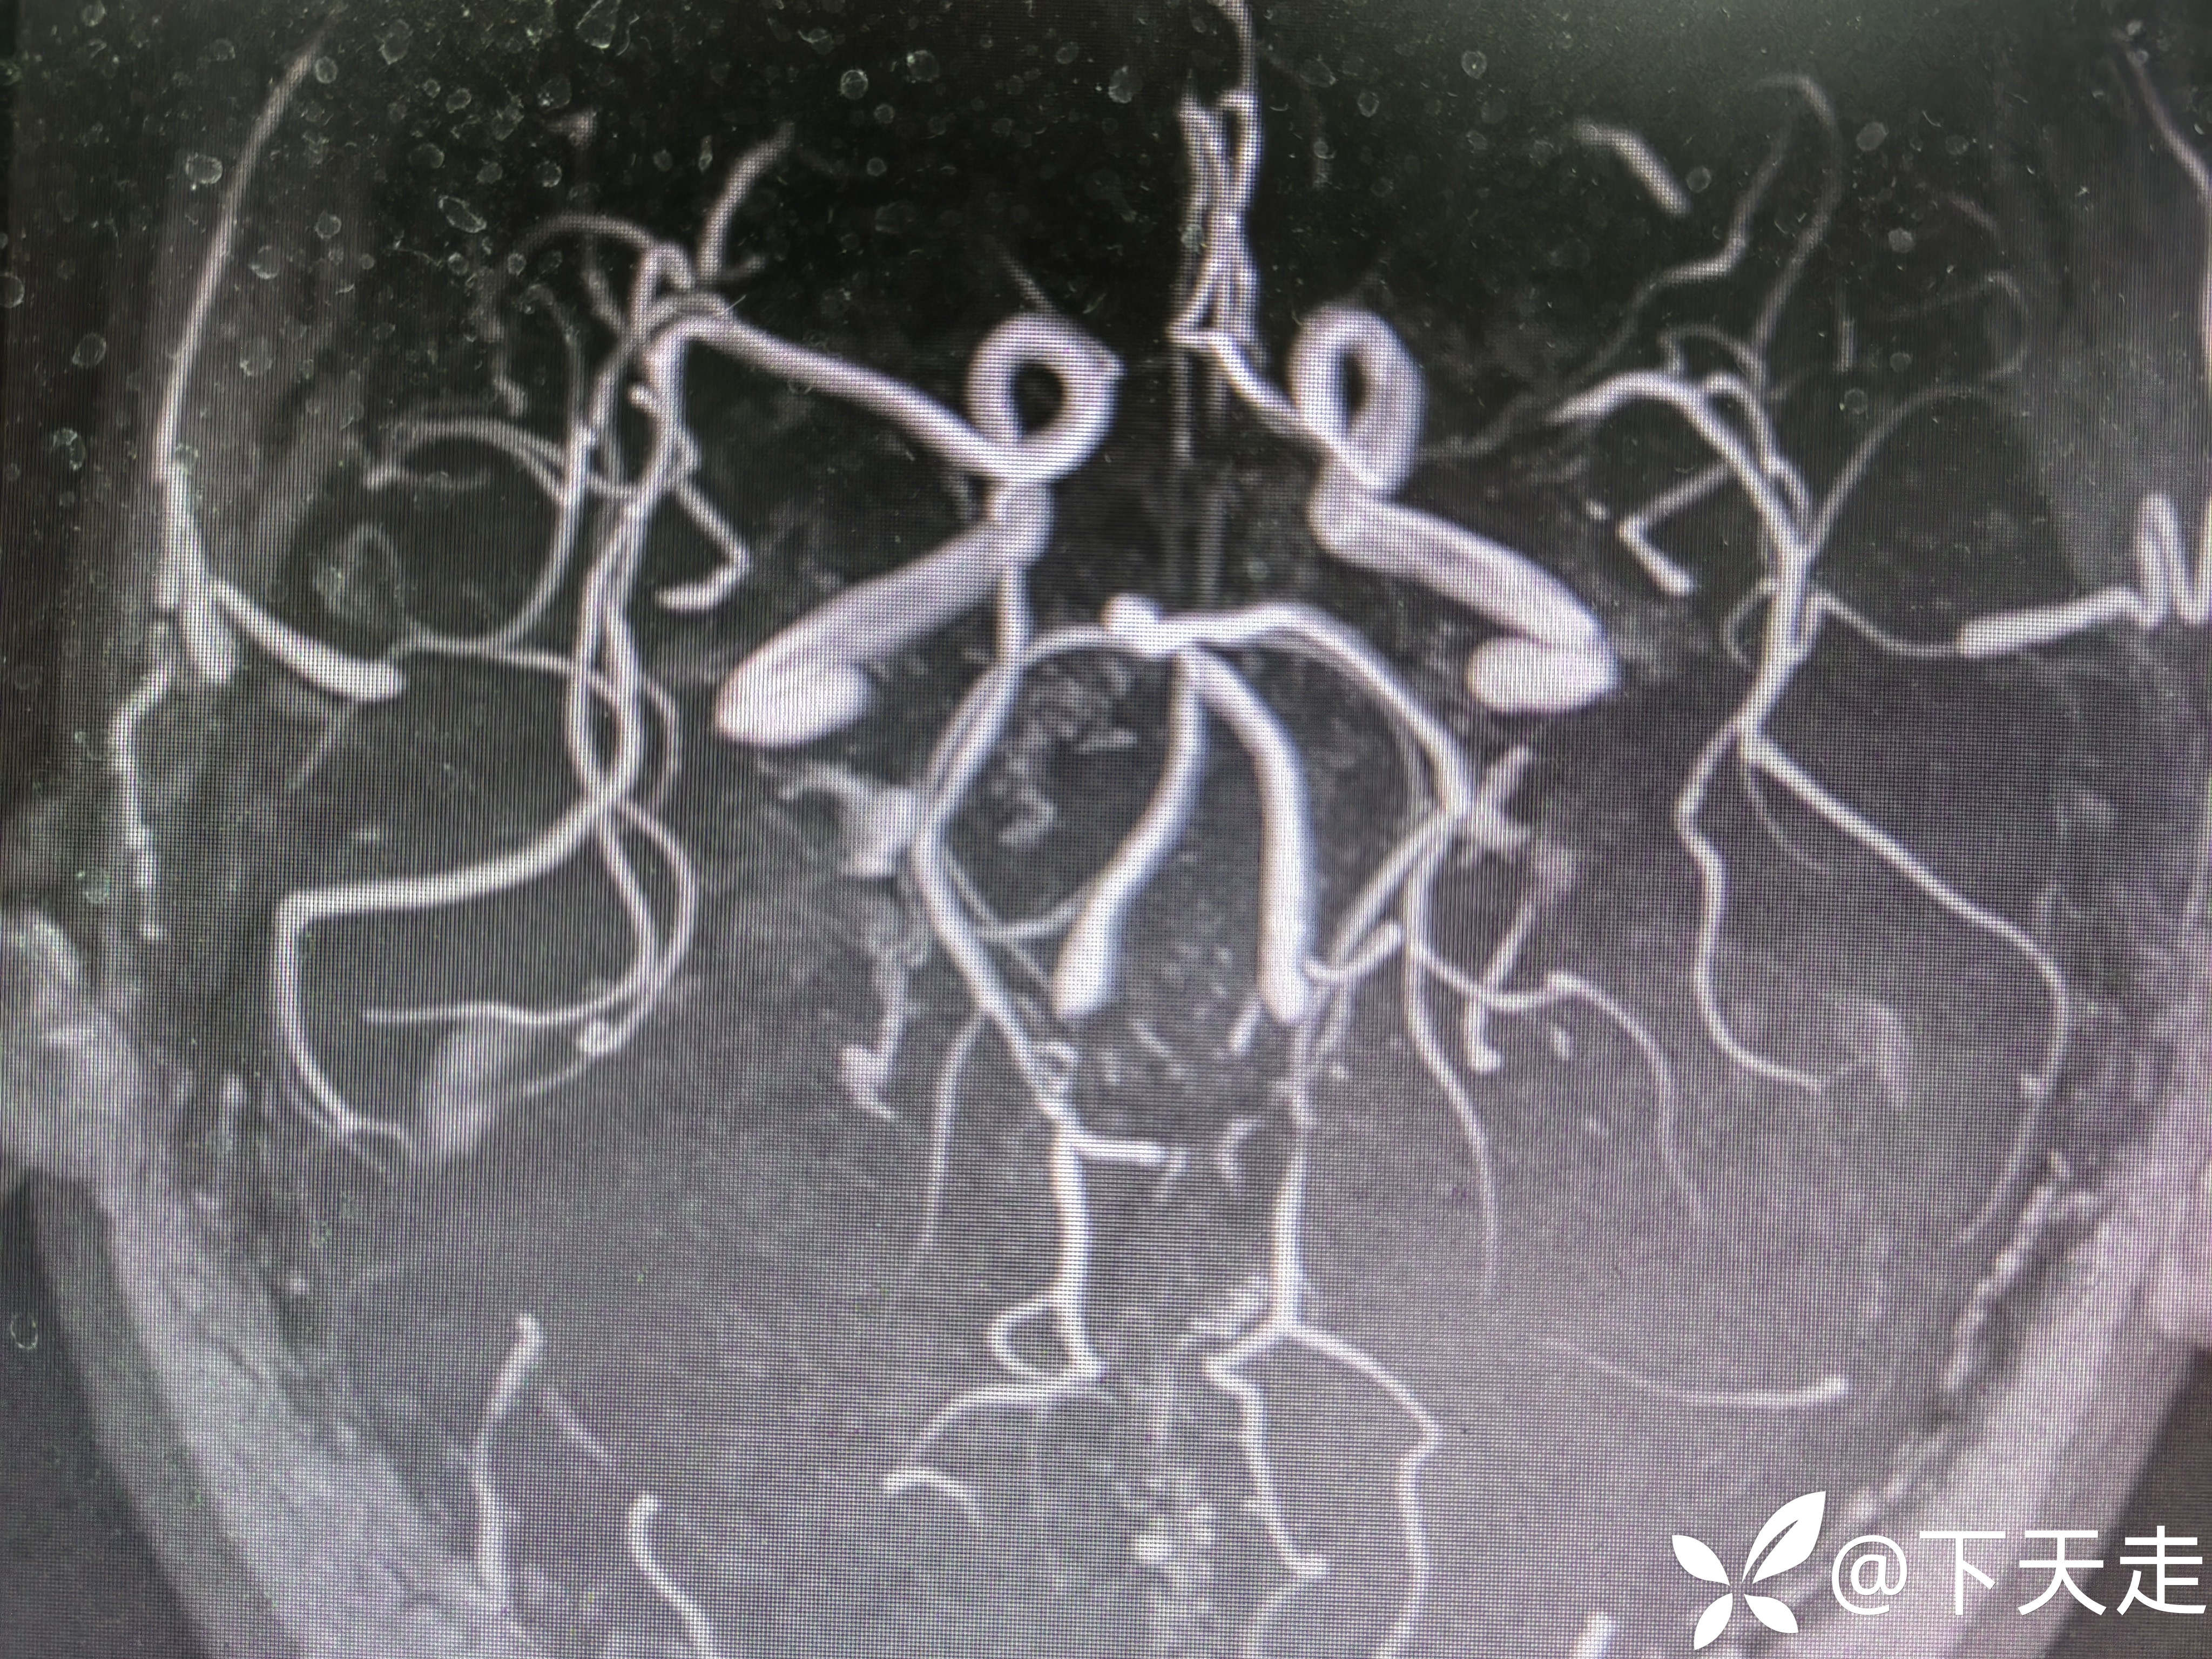

患者病情好转过程中突然加重,同一部位梗死面积扩大原因?